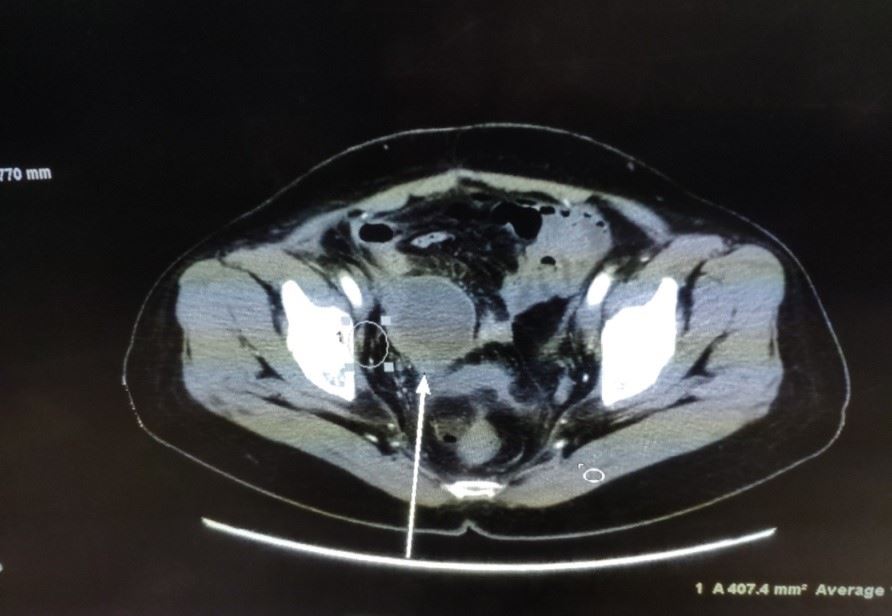

【明慧网二零二三年三月二十三日】二零一八年十月,我的表姑从美国回来就医,她患肝癌十余年,期间多次转移都通过手术切除得以缓解,但这次检查结果很悲观(见图1),是多个脏器的转移,在医院看了肿瘤外科、妇科、胃肠外科、泌尿外科等,各外科专家们均无良策!无奈之下接受了肿瘤内科主任建议的以减轻疼痛为目的的姑息性放疗。

'图1'

图1